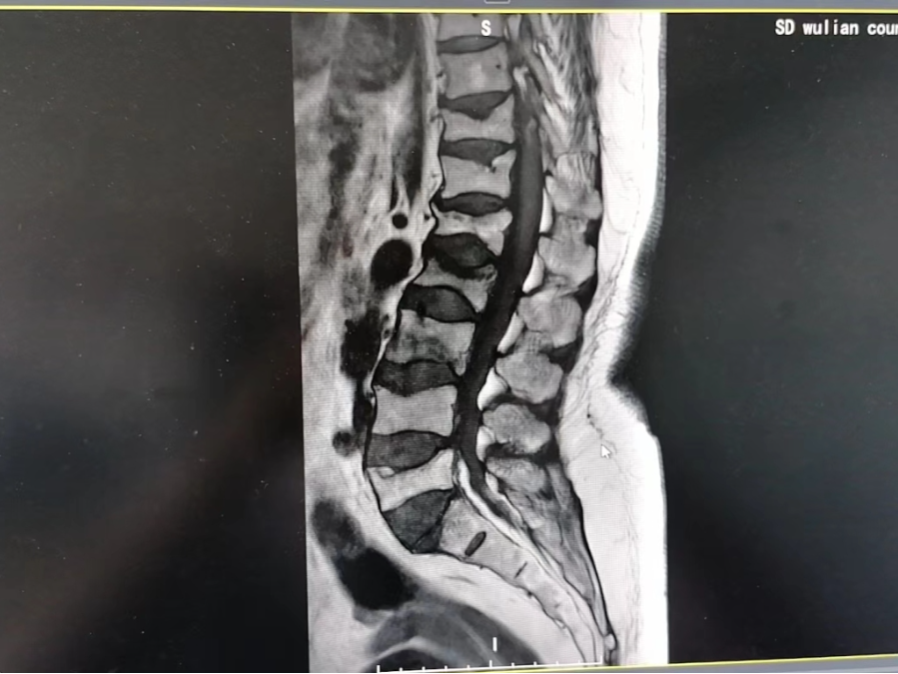

入院后结合影像结果,初步诊断为L1-L3、L5椎体压缩性骨折,T11-T12、L4椎体陈旧性压缩改变,重度骨质疏松。

(入院影像结果)